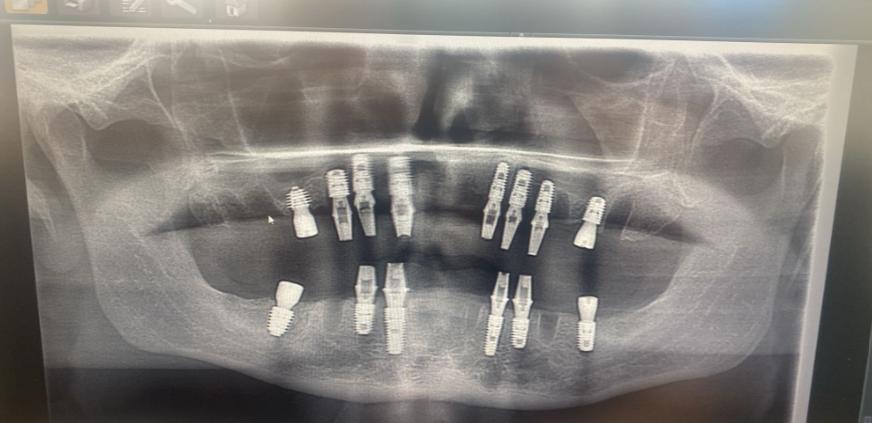

Un bărbat care a crezut că-și repară toată dantura cu 5.000 de euro în Turcia s-a întors acasă fără niciun dinte în gură

Jon Denton avea probleme dentare din 2020, în urma unui accident rutier FOTO: GoFundMe